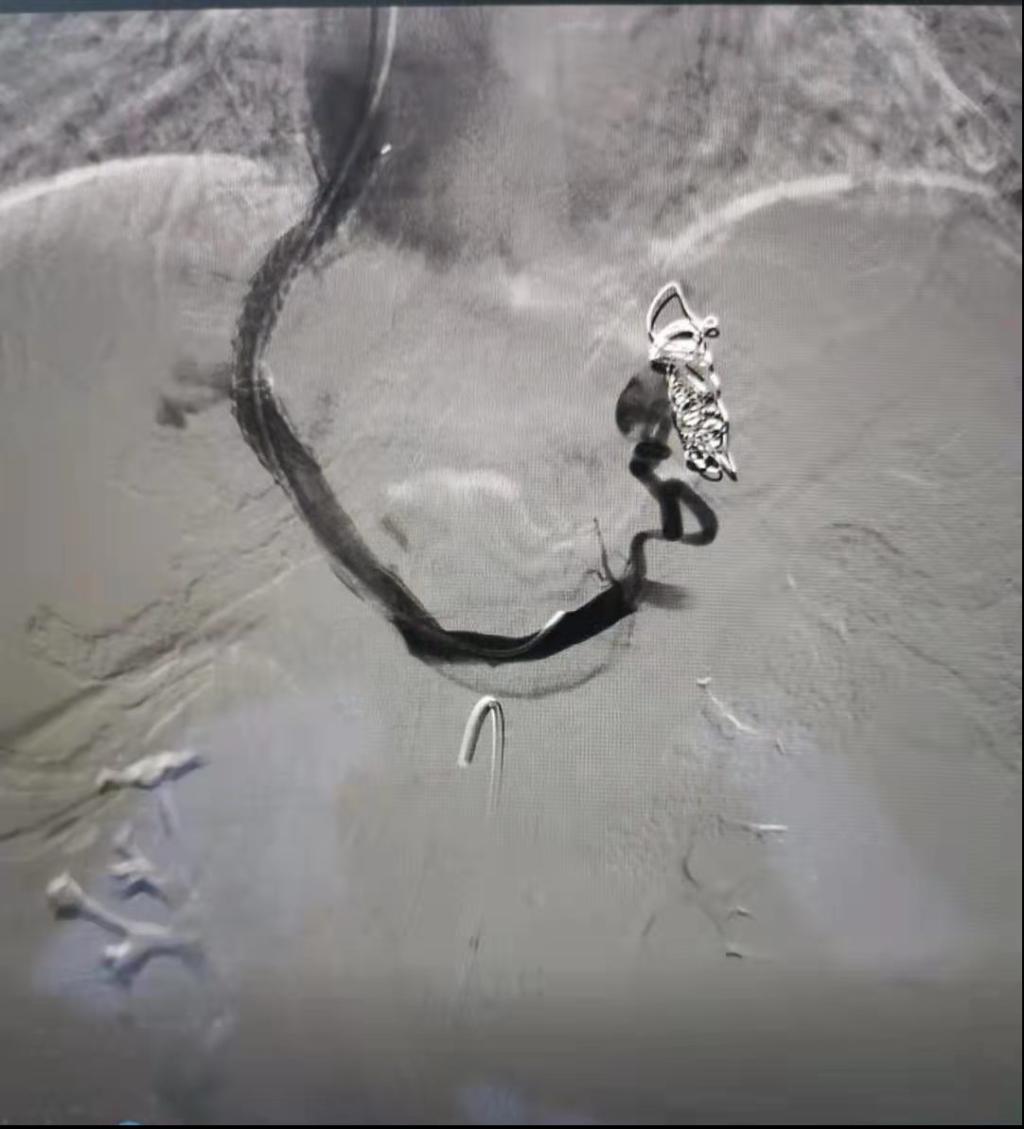

为预防患者再次出血,解决门静脉高压,消化内科医护人员经讨论后决定行TIPS术治疗。8月10日,在院领导及介入科、心内科、普外科等相关科室大力支持下,消化内科王宇晖主任、赵新功副主任医师、王亚茹护士长、常月红主管护师等组成的手术团队,在介入科顺利完成了间接门静脉造影术、TIPS支架置入术、胃冠状静脉栓塞术及脾胃肾分流道封堵术。术后患者恢复良好,第二天即可下地活动。术后复查TIPS支架通畅,第四天患者出院。

TIPS手术(经颈内静脉肝内门体静脉分流术)是治疗肝硬化失代偿期食管胃底静脉曲张出血的一把利器,是解决肝硬化失代偿期上消化道大出血最直接、有效的治疗手段。该手术可以解决患者反复出血、难治性腹水及根本上解决门脉高压问题,但因手术难度大,技术要求高,目前在我国仅少数医院开展,在陕西省能够开展的医院屈指可数。消化内科TIPS手术的开展,为渭南市肝硬化失代偿期患者带来更多生的希望,也将医院消化介入诊疗技术带入全省先进行列。